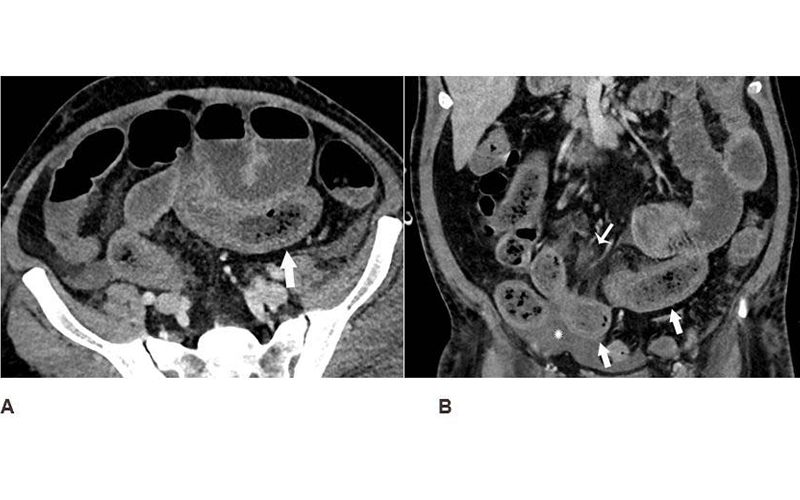

Records showed that 17% of patients had cross-sectional abdominal imaging, including 44 ultrasounds, 42 CT scans, and 1 MRI. Bowel abnormalities were seen on 31% of CT scans (3.2% of all patients) and were more frequent in intensive care unit (ICU) patients than other inpatients. Bowel findings included thickening and findings of ischemia such as pneumatosis and portal venous gas. Surgical correlation in four patients revealed unusual yellow discoloration of bowel in three of the patients, and bowel infarction (dead bowel) in two patients.

In two patients who had bowel resection, pathology demonstrated ischemia with patchy necrosis. Both had fibrin thrombi in submucosal arterioles, suggesting bowel ischemia in these patients might be caused by these small blood clots. Lung base findings led to a diagnosis of COVID-19 in one patient who presented with abdominal symptoms only. Of right upper quadrant ultrasounds, 87% were performed for liver laboratory findings, and 54% demonstrated a dilated sludge-filled gallbladder suggestive of cholestasis.

“Some findings were typical of bowel ischemia, or dying bowel, and in those who had surgery we saw small vessel clots beside areas of dead bowel,” Dr. Bhayana said. “Patients in the ICU can have bowel ischemia for other reasons, but we know COVID-19 can lead to clotting and small vessel injury, so bowel might also be affected by this.”